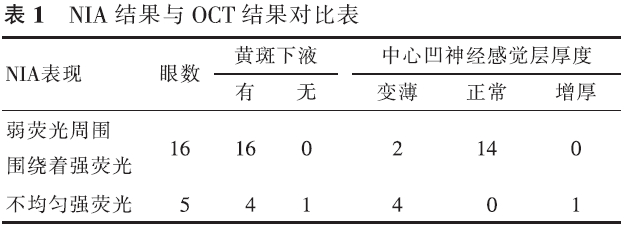

【摘要】 目的 近红外眼底自发荧光检查(NIA)联合OCT对孔源性视网膜脱离巩膜扣带术后早期黄斑结构的评估价值。方法 前瞻性系列病例研究。对21例(21眼)伴黄斑脱离的孔源性视网膜脱离患者行巩膜扣带术,于术后3个月行NIA及OCT检查。观察检查图像的异常和手术后视力的恢复情况。对视力的变化进行配对t检验,NIA与术后BCVA的相关性采用双向无序分类变量资料的关联性进行分析。结果 NIA:16眼表现为弱荧光周围围绕着强荧光,5眼表现为不均匀的强荧光。OCT:20眼存在黄斑下液;中心凹视网膜神经纤维层的厚度6眼变薄,14眼正常,1眼增厚;21眼IS/OS反射异常。视力恢复情况:术后3个月与术后1 d比较,NIA表现为弱荧光周围围绕着强荧光者,视力差异有统计学意义(t=9.922,P<0.05),NIA表现为不均匀强荧光者,视力差异无统计学意义(t=2.409,P>0.05),黄斑NIA表现与术后BCVA变化高度相关(C=0.502,P<0.05)。结论 孔源性视网膜脱离巩膜扣带术后早期,黄斑结构与功能均尚未完全恢复,需要我们加以重视。

【Abstract】 Objective To evaluate the changes in macular structure in the early stages after undergoing scleral buckling surgery for rhegmatogenous retinal detachment (RRD); to use melanin-related near-infrared fundus autofluorescence (NIA) combined with optical coherence tomography (OCT) for studing the changes. Methods This was a prospective case-series study. Melanin-related near-infrared fundus autofluorescence (NIA) and optical coherence tomography (OCT) examinations were performed on 21 patients with local primary RRD three months after undergoing a successful scleral buckling procedure for retinal reattachment. The RRDs in all 21 eyes involved the macula. To check the anomalies fo the images and the recovery of the vision after surgery. Changes invision after surgery were compared with a paired t test. The correlation of NIA and BCVA was analyzed with the relevance of two-way disorderly classification variable data. Results NIA revealed that 16 eyes had hypofluorescence surrounded by hyperfluorescence and 5 eyes had uneven hyperfluorescence. Submacular fluid was found in 20 eyes. The retinal nerve fiber layer in the central fovea became thinner in 6 eyes. In one eye, the retinal nerve fiber layer in the central fovea became thicker, and in another 14 eyes the thickness of the retinal nerve fiber layer was normal. The reflection from the photoreceptor inner and outer segment junction (IS/OS) was abnormal in all 21 eyes. Visual acuity measured with NIA revealed that the hypofluorescence which was surrounded by hyperfluorescence had improved at the 3-month follow-up compared to the 1-day follow-up examination (t=9.922, P<0.05), while VA measured at the same time revealed that uneven hyperfluorescence had not improved at the 3-month follow-up (t=2.409, P>0.05). The macular NIA results and the change in postoperative BCVA were highly correlated (r=0.502, P<0.05). Conclusion Macular function and structure do not fully recover in the early stages after undergoing scleral buckling to treat RRD. More attention should be paid to this problem.